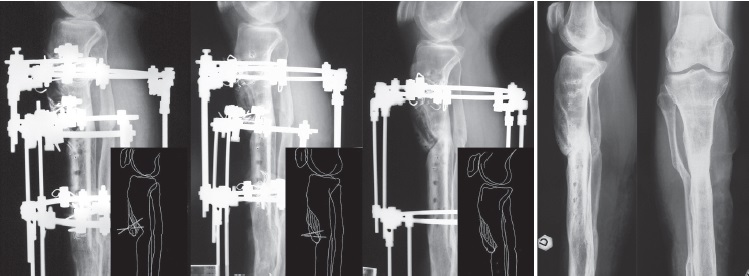

We operated this patient in seven months after the injury. First of all, we removed the hybrid external fixator. After surgical approach to the proximal third of the tibial shaft, we observed an anteromedial segment of necrotic bone; we performed a partial anteromedial resection of 8 cm (Figure 10). We performed a partial osteotomy for setting up a posteromedial segment, maintaining the continuity of the lateral aspect of the tibia. The posteromedial fragment was fixed with three 1.8 mm K-wires specially bent into a pigtail. We finally applied the Ilizarov apparatus to ensure stability (Figure 11). The fragment was progressively transported from posterior to anterior to fill the defect (Figure 12). The frame was removed less than in 4 months after the surgery when union was achieved. The patient’s last follow-up was at two years and a half after frame removal with no reported recurrence of infections or other complications.

Figure 10. Partial resection of an 8 cm long anteromedial segment of necrotic bone

Figure 11. The posteromedial fragment was fixed with three 1.8 mm K-wires specially bent into a pigtail. The Ilizarov apparatus was applied to the leg to ensure stability

Figure 12. The posteromedial fragment was gradually distracted from posterior to anterior to fill the partial defect. Note complete union and remodeling at the last follow-up